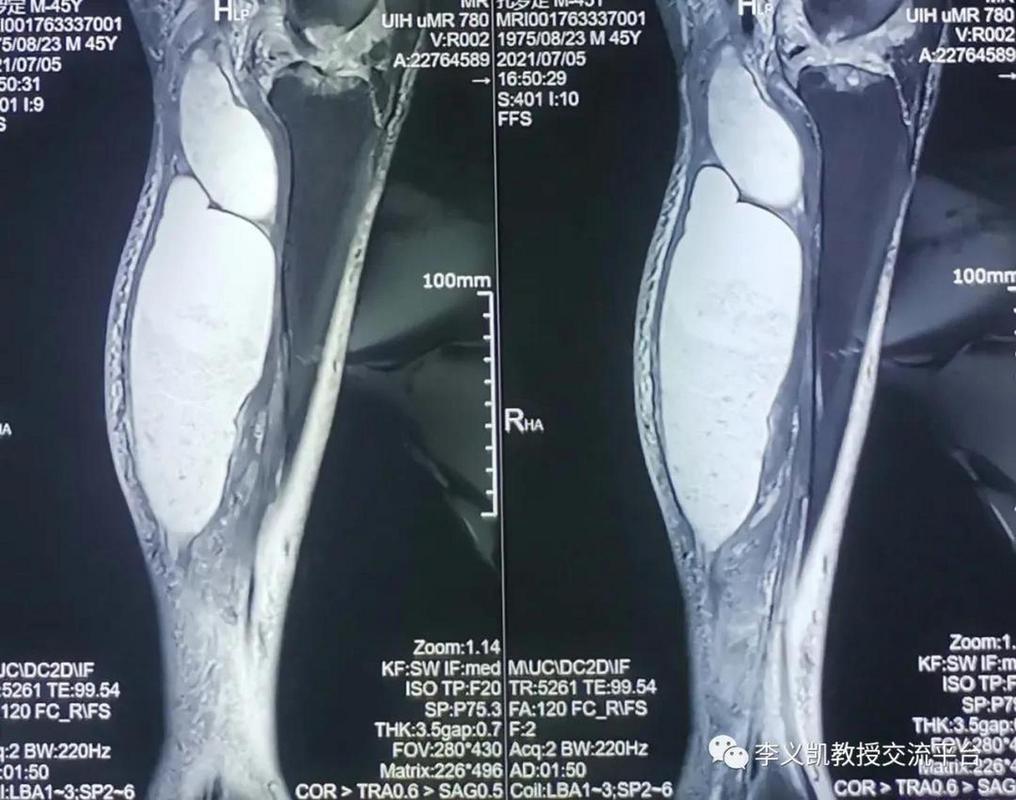

肌腱炎和腱鞘炎

类风湿常影响关节周围的肌腱和腱鞘,导致疼痛和功能障碍,MRI可以显示肌腱的肿胀、炎症、撕裂或腱鞘积液。